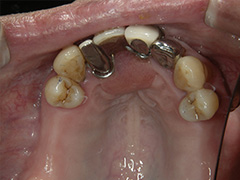

Case.3 コーヌスクローネ義歯すれ違い咬合症例(装着後11年経過)

初診時、他院で入れ歯を何回作り直しても、歯の向きが斜めになってしまい、入れ歯もすぐ外れて困っていた患者様です。

初診時、他院で作製した入れ歯と口腔内状態。

当院で製作した入れ歯を外した口腔内

治療後、当院で作製した入れ歯と口腔内状態(治療後8年経過時)

年齢層 | 60代 女性 |

どんなお悩み | かぶせ物を外して、残ってる歯に二重に冠をかぶせて入れ歯をとめる義歯を制作(コーヌスデンチャー) |

治療 期間 | 治療期間は3か月程度 |